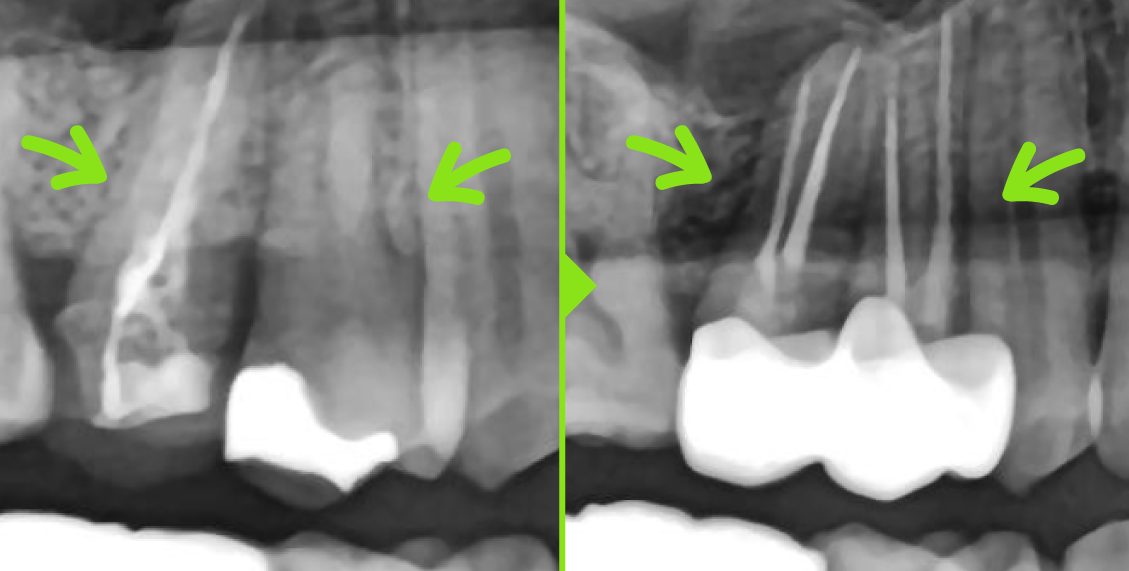

[※ 본 이미지는 연세화이트치과 환자분의 동의를 받아 촬영 및 게시된 사진입니다. 동일한 질환이라도 개인의 구강 상태와 치아 구조, 염증 정도 등에 따라 치료 방법 및 결과, 부작용에는 차이가 있을 수 있습니다. 본 내용은 의료법 제56조 제1항을 준수하여 작성된 의료 정보 제공 목적의 콘텐츠입니다.] 타 치과 신경치료 후 약 6개월이 지난 시점에서뿌리 끝 염증이 남아…